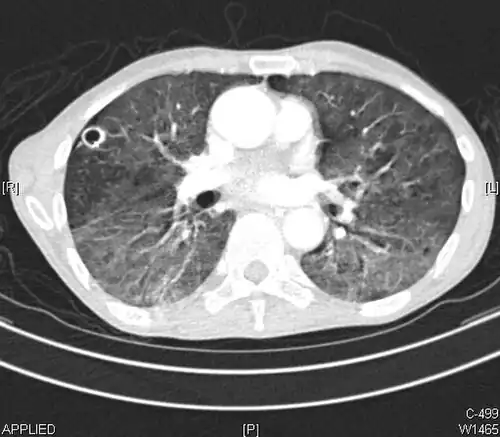

High-resolution CT image showing ground-glass opacities in the periphery of both lungs in a patient with COVID-19 (red arrows). The adjacent normal lung tissue with lower attenuation appears as darker areas.

CT image in patient with COVID-19 showing bilateral ground-glass opacities at the periphery of both lungs.

Ground-glass opacity is among the most common imaging findings in patients with confirmed COVID-19.[16][17] One systematic review found that among patients with COVID-19 and abnormal lung findings on CT, greater than 80% had GGOs, with greater than 50% having mixed GGOs and consolidation.[16] GGOs with mixed consolidation has most often been found in elderly populations.[18]

Several studies have described a pattern among initial, intermediate, and hospital discharge imaging findings in the disease course of COVID-19. Most commonly, initial CT imaging reveals bilateral GGOs at the periphery of the lungs. During initial stages, this is most often found in the lower lobes, although involvement of the upper lobes and right middle lobe has also been reported early in the disease course.[16][18] This is in contrast to the two similar coronaviruses, SARS and MERS, which more commonly involve only one lung on initial imaging.[19][20] As the COVID-19 infection progresses, GGOs typically become more diffuse and often progress to consolidation.[11][18] This is sometimes accompanied by the development of a crazy paving pattern and interlobular septal thickening.[18] In many cases the most severe pulmonary CT abnormalities occurred within 2 weeks after symptoms began.[17] At this point, many individuals begin showing resolution of consolidation and GGOs as symptoms improve. However, some patients have worsening symptoms and imaging findings, with further increase in septal thickening, GGOs, and consolidation. These patients may develop lung "white-out" with progression to acute respiratory distress syndrome (ARDS) requiring treatment escalation.[17][21]